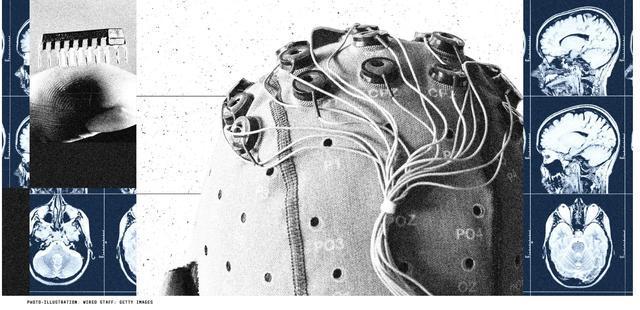

美国知名科技媒体《连线》(Wired)杂志网站近日发表的一篇文章,聚焦中国本月发布的脑机接口政策文件。文章认为,这份文件彰显了中国在脑机接口领域成为全球领导者的雄心壮志。

文章认为,脑机接口通过读取和解码大脑的神经活动,将其转化为指令。由于它们在大脑与外部设备之间建立了直接连接,因此作为严重身体残疾人士的辅助设备具有巨大的潜力。

文章称,脑机接口的研究可以追溯到20世纪70年代,但几十年来,这项技术在实际应用中一直面临复杂性和可靠性不足的挑战。中国涉足脑机接口研究的时间较晚,但正在迅速赶上美国。中国的多家公司和研究机构已成功在患者身上测试了脑机接口植入设备,展示了瘫痪患者能够通过脑机接口移动电脑屏幕上的光标、操作机械臂以及输入文字的能力。去年,中国还发布了《脑机接口研究开云电竞官方网站伦理指引》。如今,其最新政策文件为加快这些设备的开发制定了路线图。